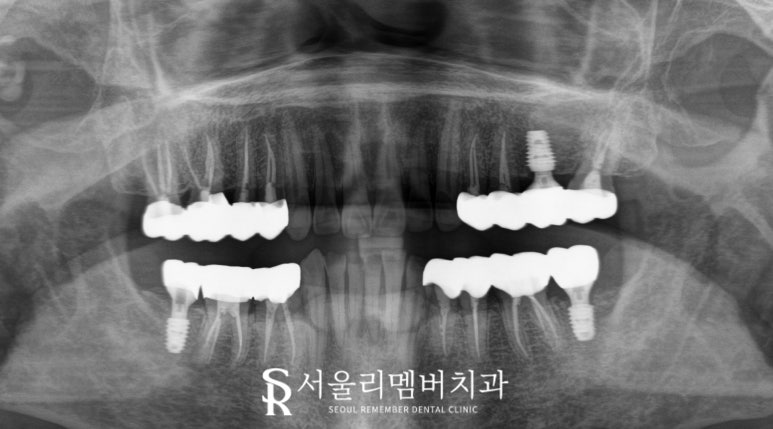

2025.05.20

구체적으로 상악 우측 소구치와 대구치 부위인

14, 15, 16, 17번,

상악 좌측 소구치와 대구치인 24, 25, 27번,

하악 우측 소구치와 대구치인 34, 35, 36번,

그리고 하악 좌측 소구치와 대구치인 44, 45, 46번에

신경치료 후 크라운 치료를 시행했습니다.

이미 결손되어 있거나

잇몸뼈가 심하게 녹아버린 부위는

임플란트를 계획했는데요,

상악 좌측 대구치인 26번,

하악 우측 대구치인 37번,

하악 좌측 대구치인 47번에

임플란트를 식립하여 결손된 부위를 대체했습니다.